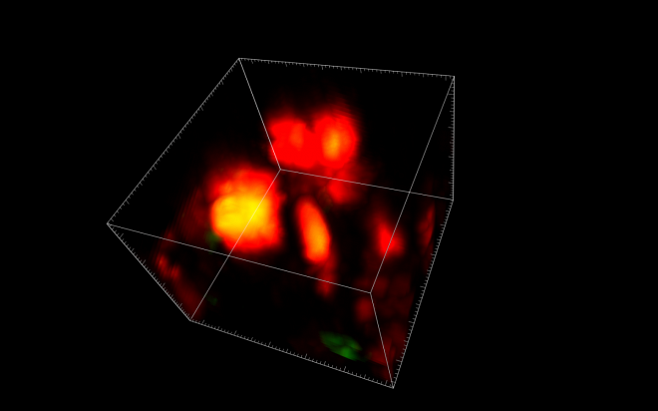

Использовав технологию интравитальной визуализации, учёные смогли заглянуть глубоко внутрь живой костной ткани, где они обнаружили, что остеокласты не просто умирают после выполнения своей работы, но делятся на более мелкие клетки, прежде чем переродиться. Заинтересовавшись находкой, исследователи использовали секвенирование РНК для установления её генетического профиля.

«Профиль генов, которые были включены в этих клетках, был действительно интересным - в то время как многие гены также экспрессировались остеокластами, некоторые были уникальными, – рассказал автор исследования доктор Вэн Хуа Ху. – Это, вместе с доказательствами новых процессов повторного слияния, наблюдаемых с помощью интравитальной визуализации, убедило нас в том, что мы открыли новый тип клеток, который мы назвали остеоморфами, в честь Могучих рейнджеров-морфинов».

Дальнейшие эксперименты показали, что 17 из 40 обнаруженных генов остеоморфов влияют на размер и прочность костей, будучи связанными с вариантами генов, которые отвечают за минеральную плотность ткани и могут провоцировать развитие таких состояний, как дисплазия скелета. В будущем открытие планируется использовать для изучения новых подходов к лечению остеопороза и других скелетных заболеваний.

Фото: Dr Michelle McDonald